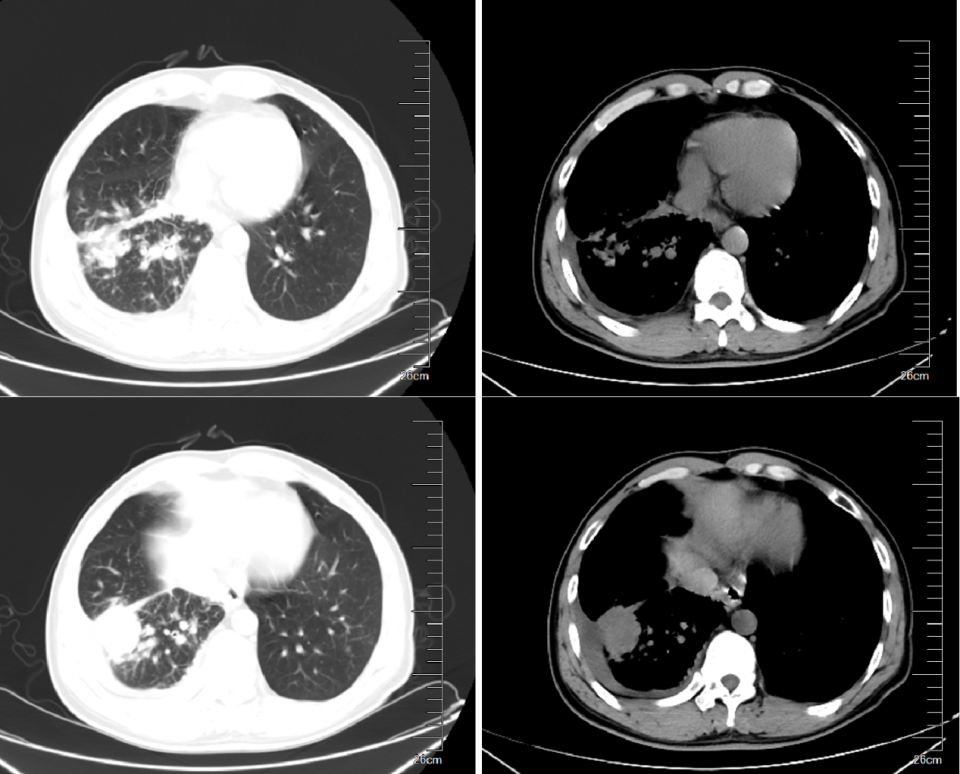

• 2022 年 12 月 19 治疗 周期)胸部 CT 示:双肺纹理增多,右肺下叶见大小约 2.3cm × 1.8cm 不规则形结节灶,边缘毛糙,可见毛刺,内似见空洞,邻近胸膜牵拉,双肺另见片絮状、条索状密度增高影,所见段及段以上支气管开口通畅,纵隔内及双侧肺门未见肿大淋巴结,双侧胸腔未见异常。疗效评估为 PR。

• 2023 年 月 22 治疗 周期)、202312 月 12治疗13 个月)、2024 年 6 月 18 日治疗 19 个月)、2024 年 12 月 22 日治疗 25 个月)、2025 年 10 月 17 日治疗 35 个月),历次复查胸部 CT 示右肺下叶不规则形结节灶大小分别为 2.2 cm × 1.3 cm、1.9 cm × 1.0 cm、2.0 cm × 1.1 cm、2.0 cm × 1.1 cm,疗效评估为维持 PR。

图 1. 2022 年 10 月 22 日患者治疗前胸部 CT 检查结果

图 2. 奥希替尼 + 化疗治疗期间胸部 CT 检查结果